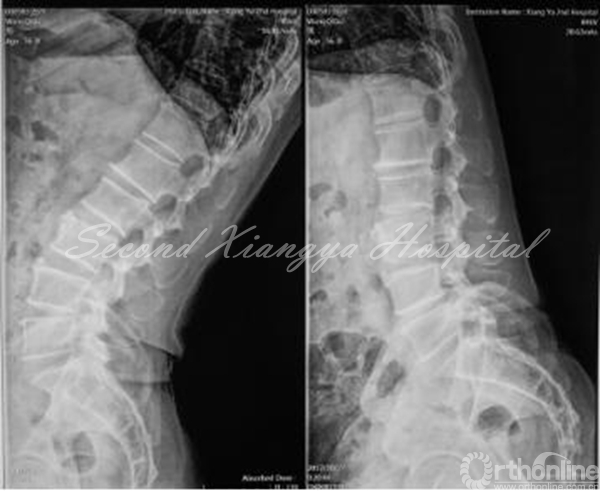

动力伸位、动力屈位